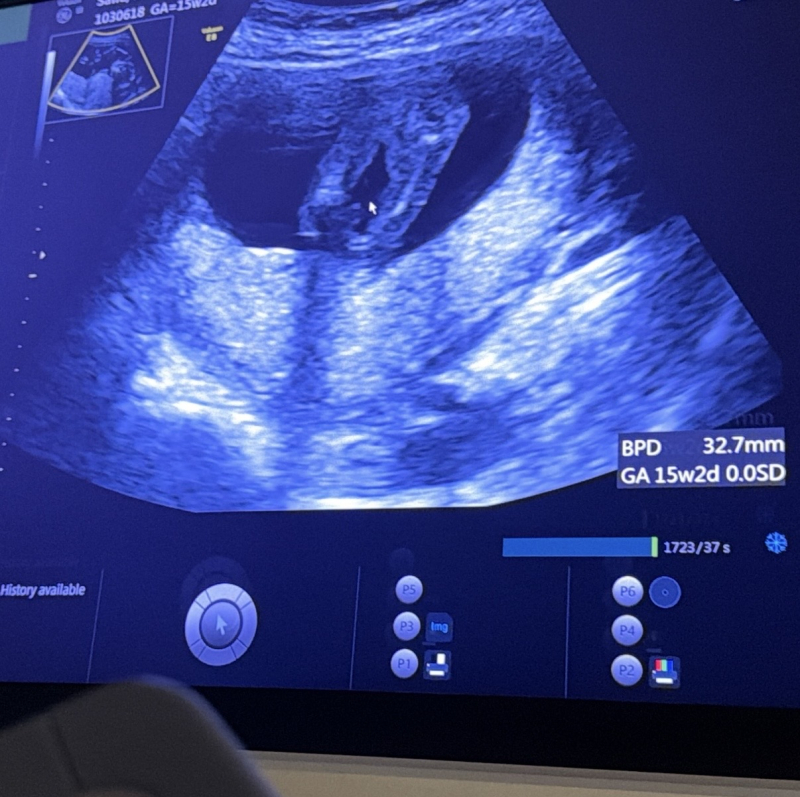

現在15w2dの妊婦です。

今日検診でおそらく女の子かなーと言われましたが

1つ目の写真は今お股になにもないように見えますが

2つ目の写真にはシンボルがついてるのかな?とも思います。

男女どちらの可能性が高いか、

今の時点での高塚先生の見解をお伺いしたいですm(_ _)m